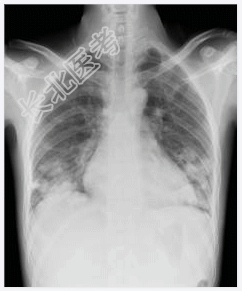

- [材料题] 男性,32岁,发热伴咳嗽、咳血丝痰一个多月,发热波动于38~39℃,外院拟肺炎抗炎治疗效果不著,入我院诊治。无盗汗,无咯血,体重下降10多斤,大小便正常。吸毒病史抽烟史10年。一般情况:无特殊。体查:右下肺湿啰音(小水泡音),二、三尖瓣听诊区闻及收缩期吹风样杂音2/6级。血常规:WBC 10.4,Ne82%。彩超:右心感染性心内膜炎,三尖瓣赘生物,重度三尖瓣漏,心包积液。痰肿瘤细胞学报告:未找到癌细胞。痰培养:无Ⅱ甲菌生长。